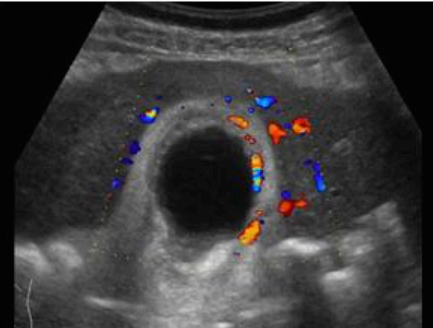

급성담낭염 US finding

- color doppler 시 GB wall 혈류증가 GB lumen bile sludge (내부에코증가)